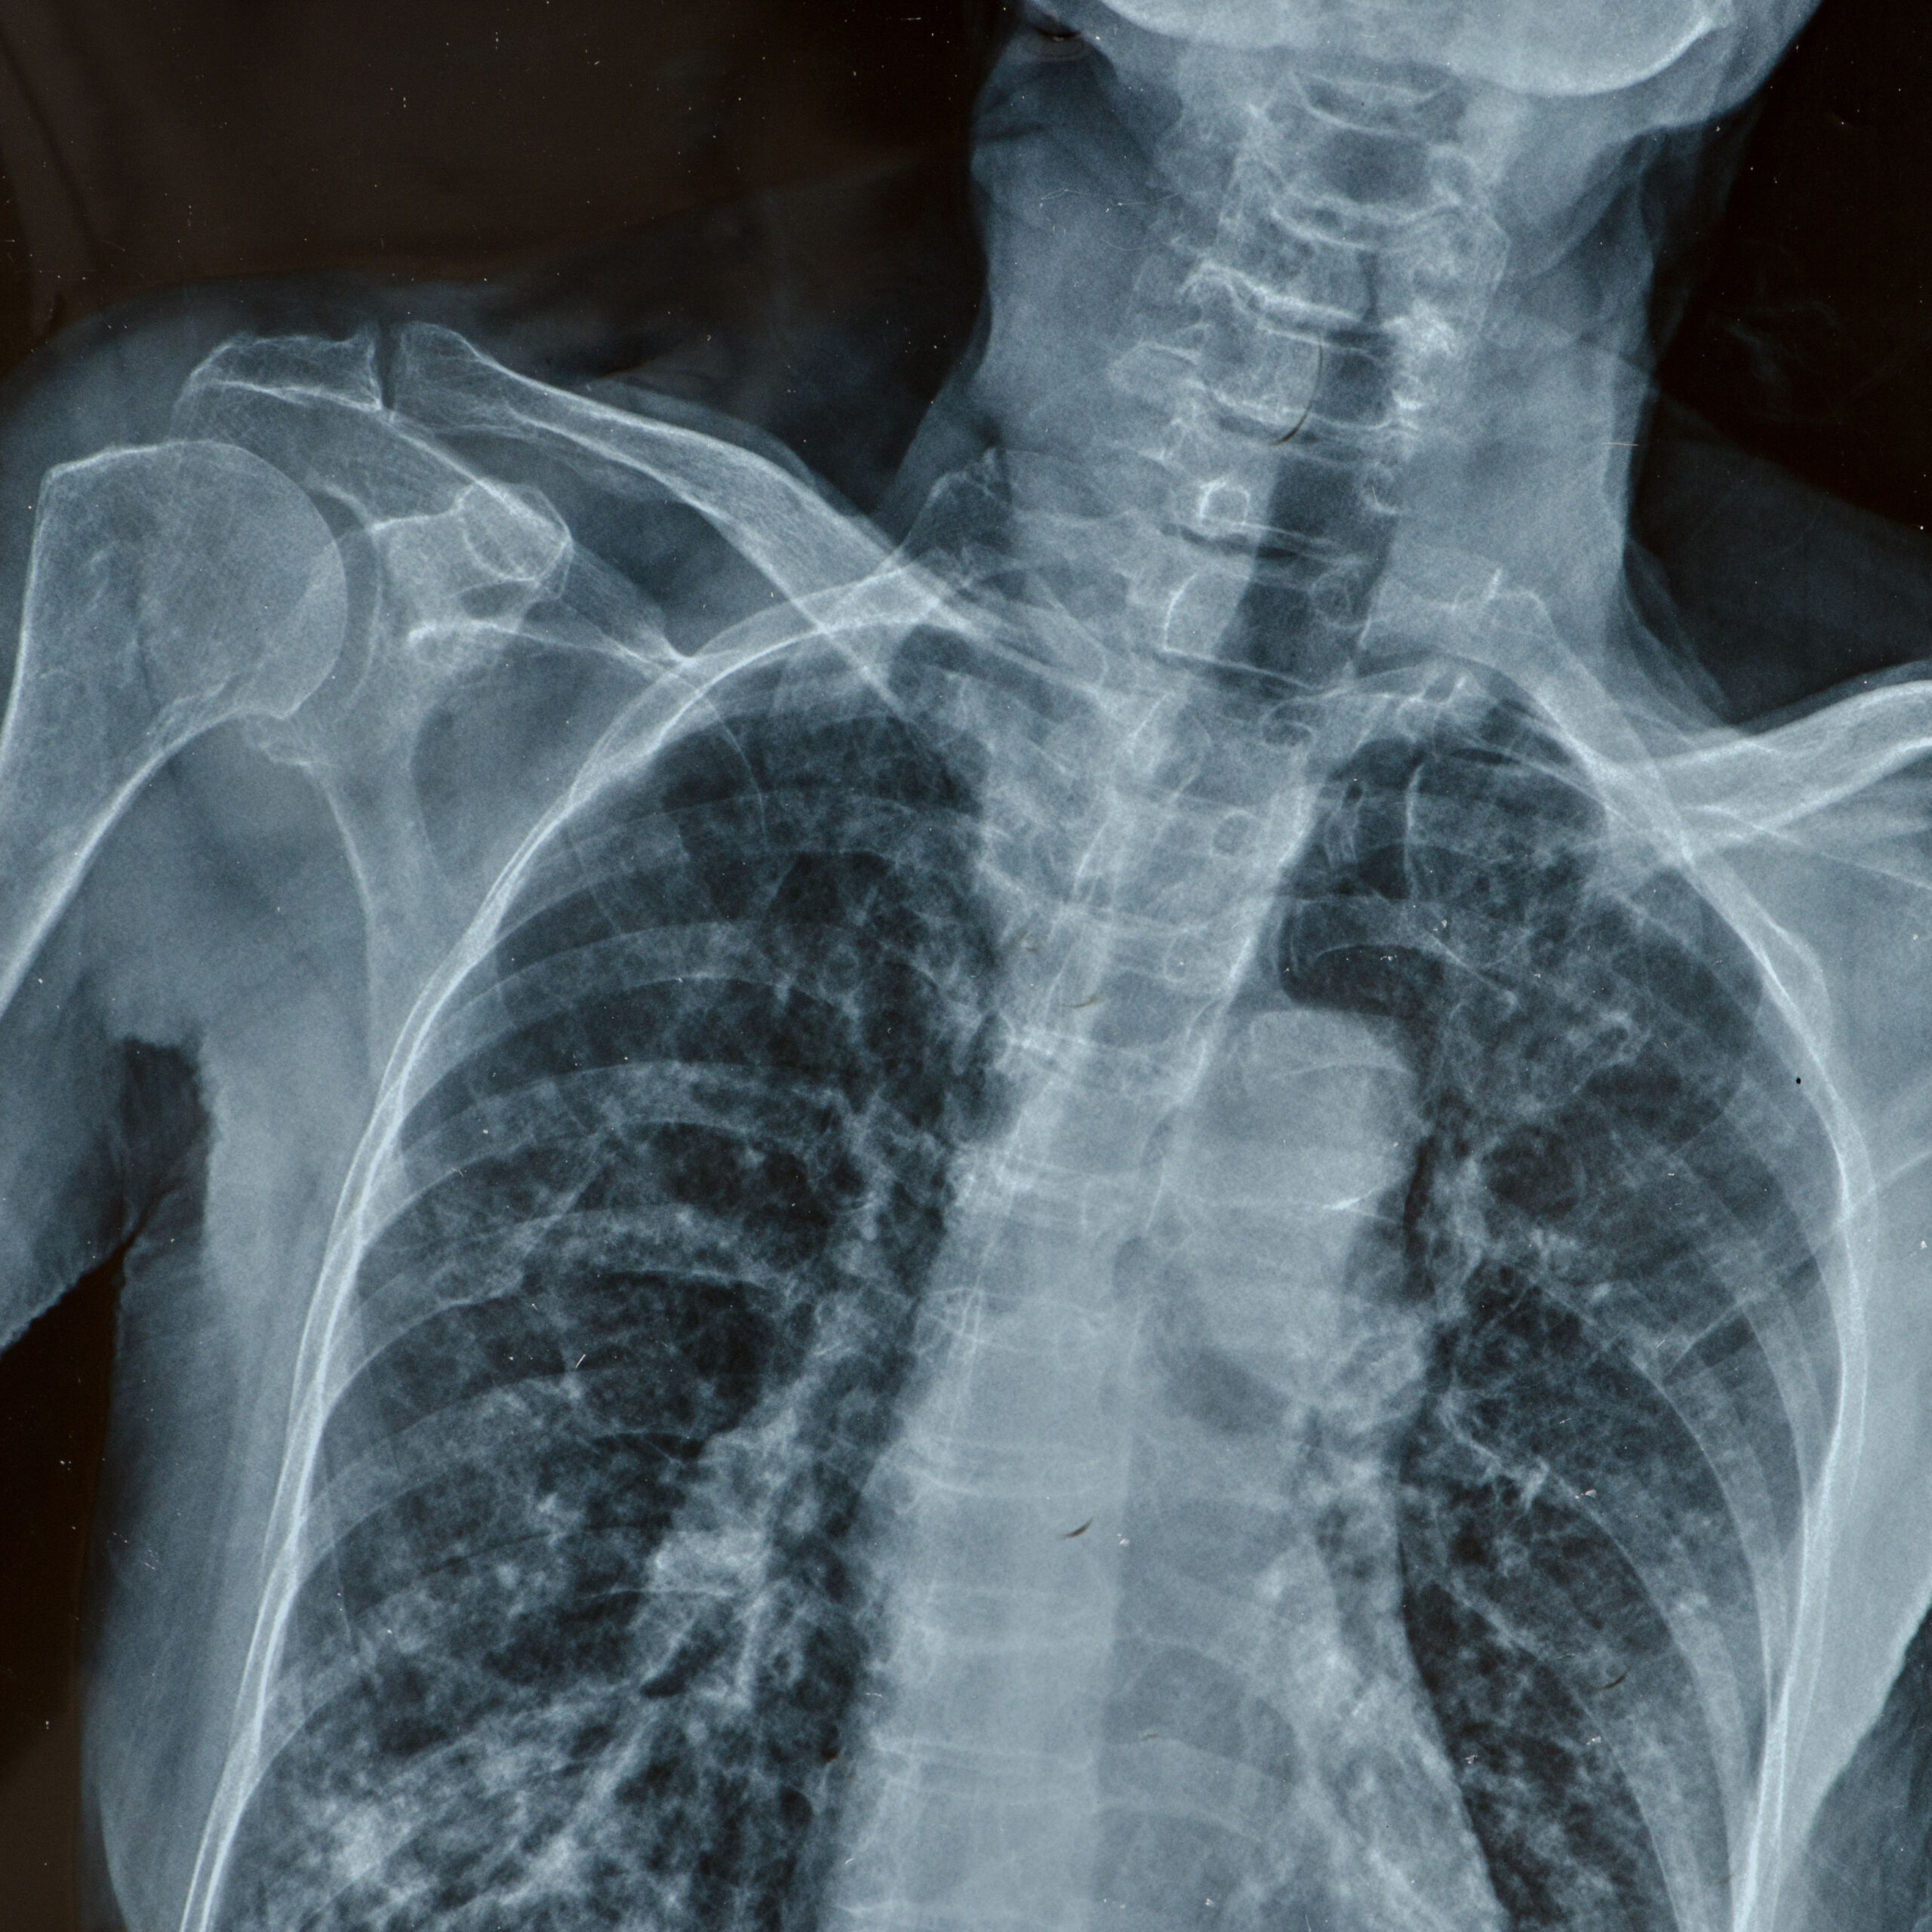

Philippa was eventually taken to A&E by his wife three days after his GP visit, now barely able to walk, doubly incontinent and in excruciating pain. An urgent MRI confirmed a massive central disc prolapse at L4/5 compressing the cauda equina nerve roots. Emergency decompression surgery was performed the following morning, but the cumulative delay caused by repeated medical negligence had already resulted in irreversible nerve root damage.